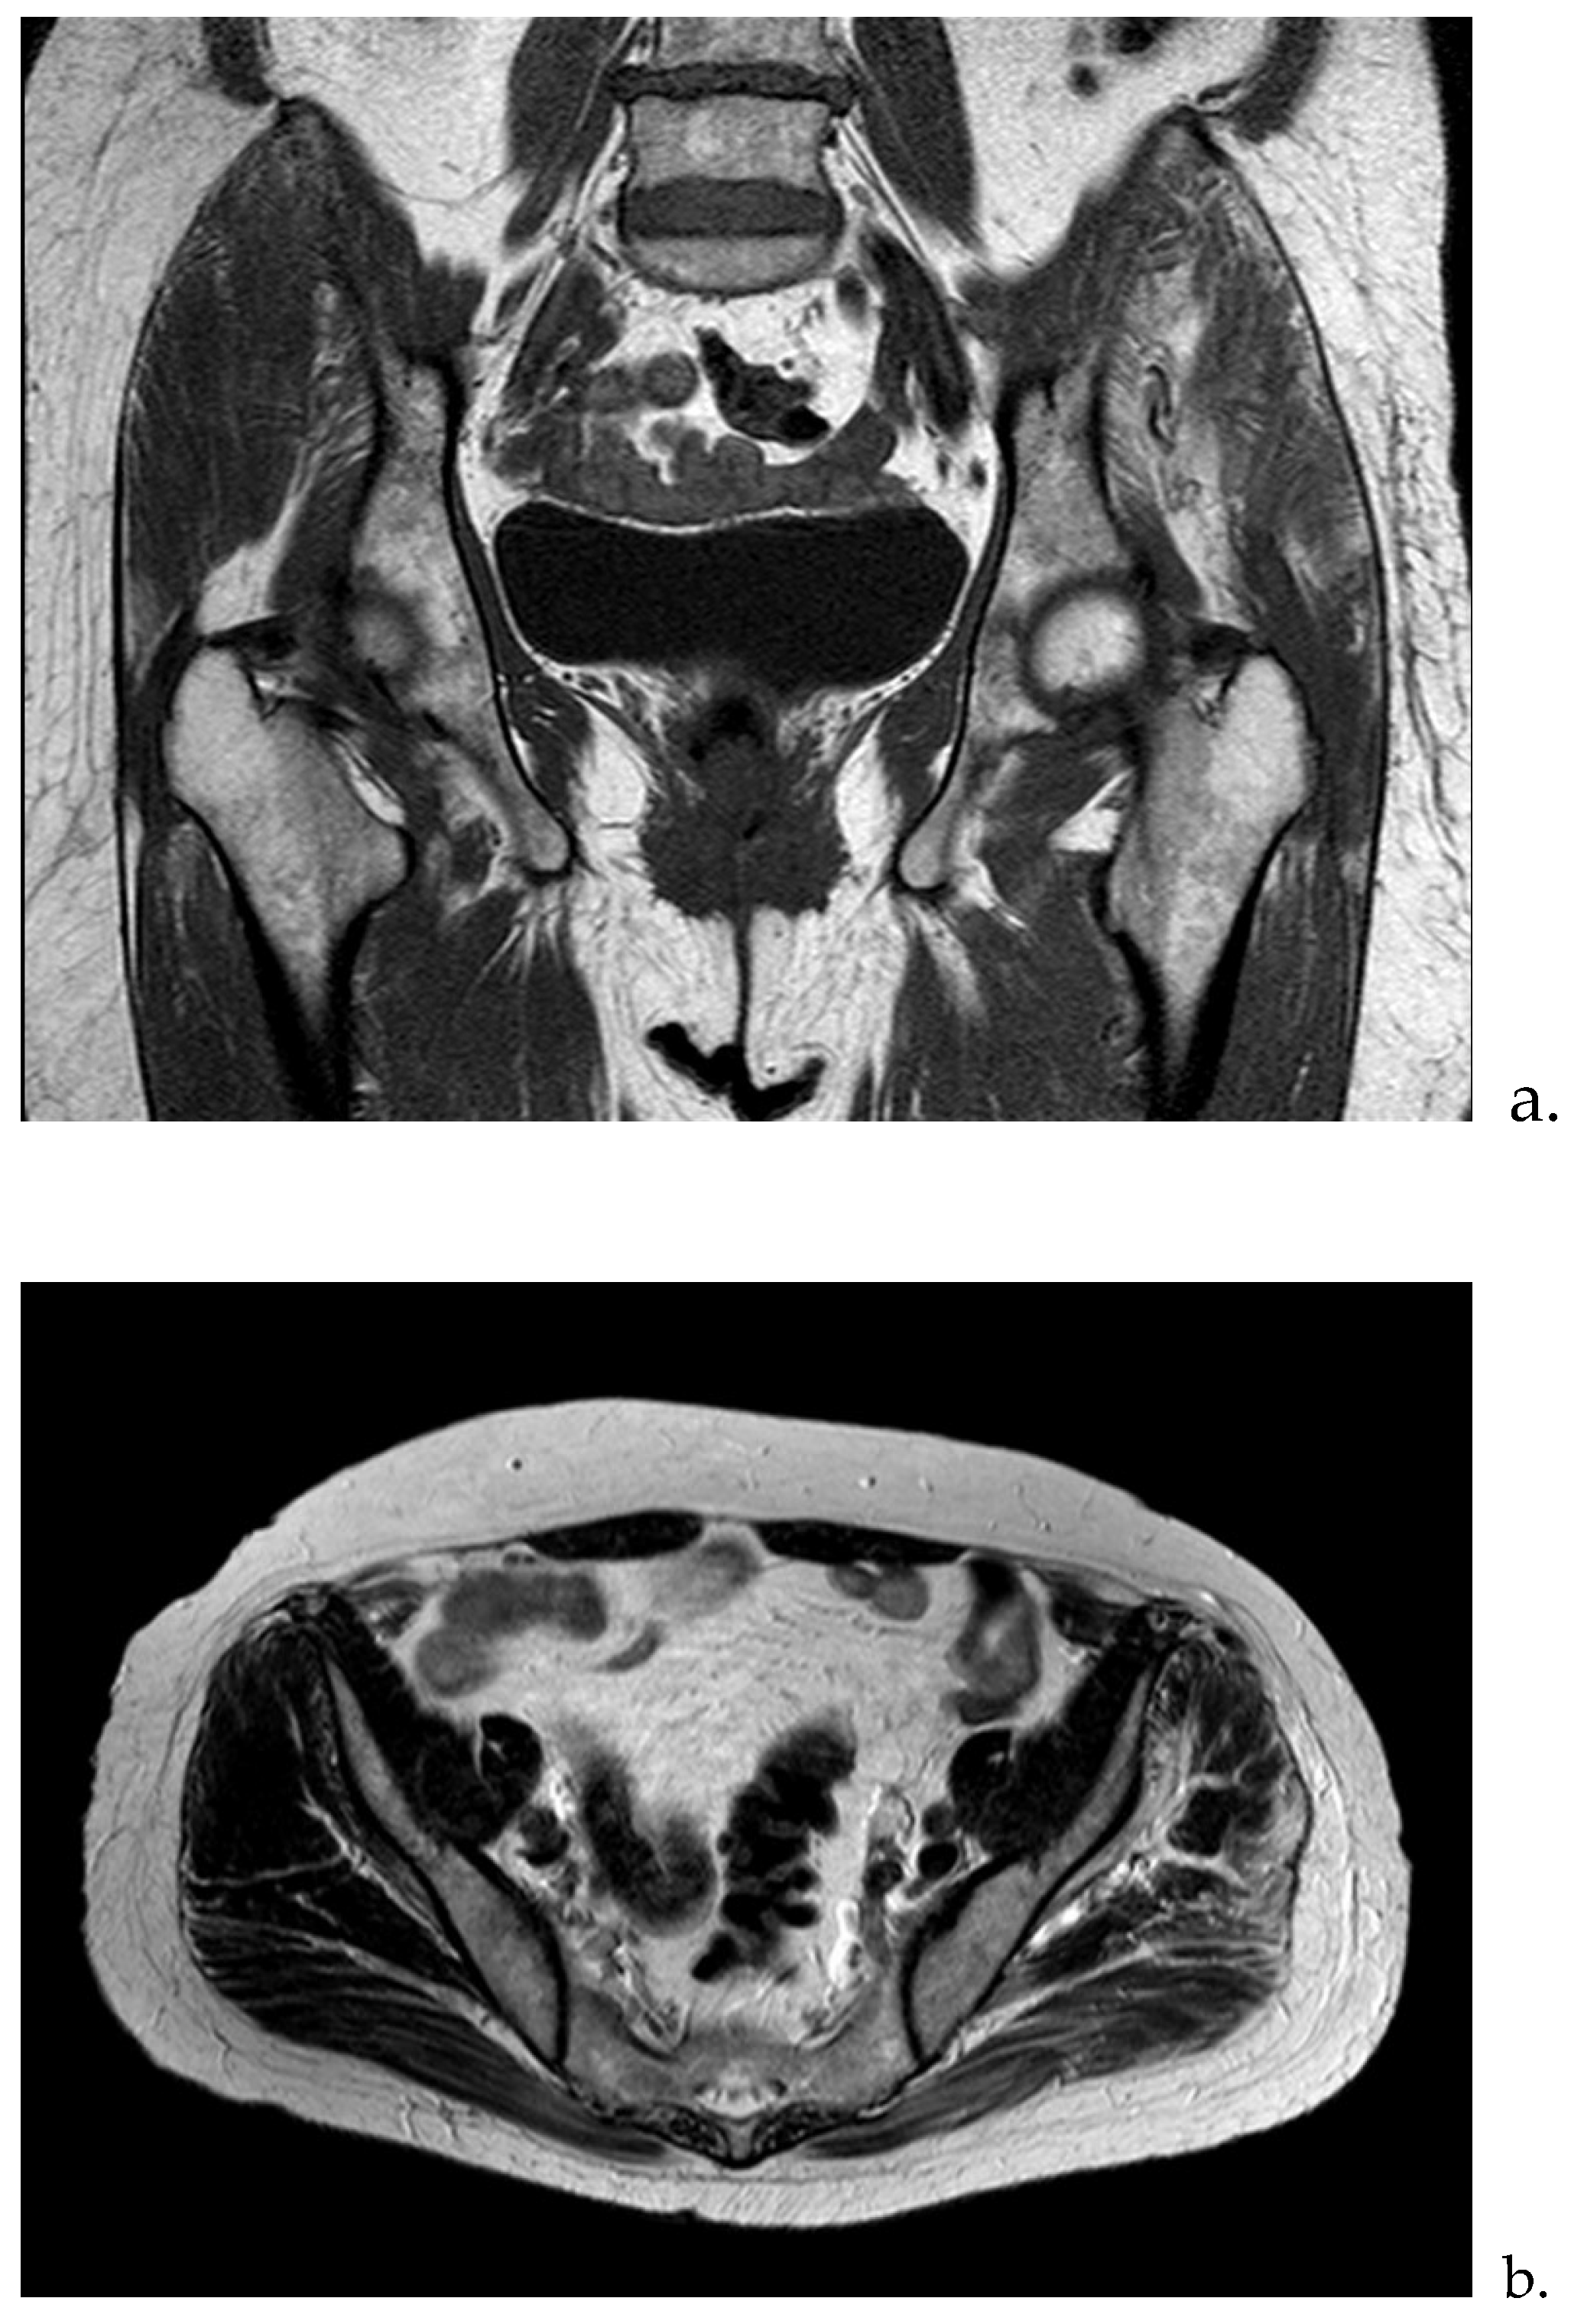

Complementary Test Results: Laboratory analysis: ESR: 80 mm/hr; Hemoglobin: 12.8 g/dL; Urea: 57 mg/dL; Creatinine: 0.93 mg/dL; GOT (AST): 16 U/L; GPT (ALT): 10 U/L; GGT: 13 U/L; CRP: 1.8 mg/dL; CPK: 563 U/L; Aldolase: 3.6 U/L (<7.6). Imaging studies: Ultrasound: Altered signal in the gluteus maximus and medius muscles. MRI: Signal abnormalities with enhancement involving the gluteus maximus and medius, consistent with findings of myositis. Etiologies considered include infectious or inflammatory origins, with traumatic causes deemed less likely (Figure 1a,b).

Figure 1. FSE STIR MRI of the left thigh in coronal view demonstrating patchy feathery STIR signal intensity seen throughout the left thigh in gluteus musculature with minimal superficial perifacial STIR signal within the superficial soft tissues. (a) coronal section and (b) transverse section.